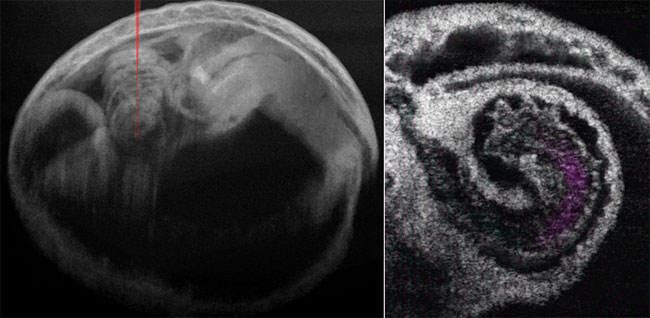

4D OCT Helps to Solve Mystery of Early Embryonic Heartbeat

Scientists from Stevens Institute of Technology and Baylor College of Medicine used 4D optical coherence tomography (OCT) to study the pumping mechanism underlying the developing mammalian heart. 4D OCT allowed them to investigate the functional relation between blood flow and heart wall dynamics within different regions of the embryonic heart at a level of detail not currently accessible by other methods. 4D OCT could potentially enable scientists to assess cardiac pumping over embryonic development as the heart tube remodels, which could reveal functional changes during early cardiogenesis that lead to congenital heart defects.